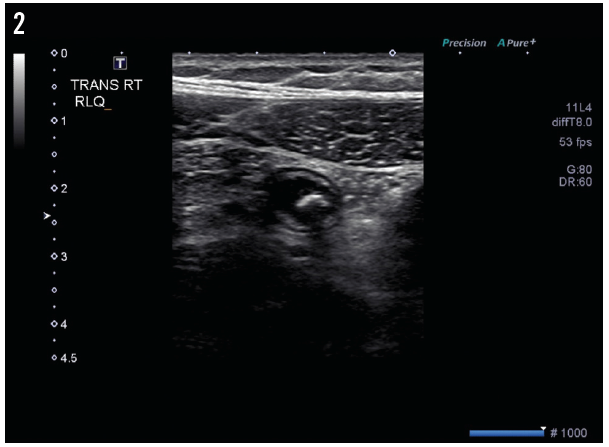

The results of pelvic ultrasonography (Figure 1) showed an elongate, tubular, noncompressible bowel loop in the right lower quadrant, measuring 8 mm, likely representing the appendix with a blind end, and suggesting acute appendicitis with appendicolith but without evidence of perforation. A cross-sectional scan (Figure 2) showed no free fluid or periappendicular fluid collection that would suggest perforation; it also demonstrated the “ring of fire” due to the high vascularity of the inflamed appendix (Figure 3).

Figure 3. A cross-sectional scan showed a tubular structure—the appendix with appendicolith. The high vascularity of the inflamed appendix creates a “ring of fire” appearance on cross-sectional ultrasonography images.